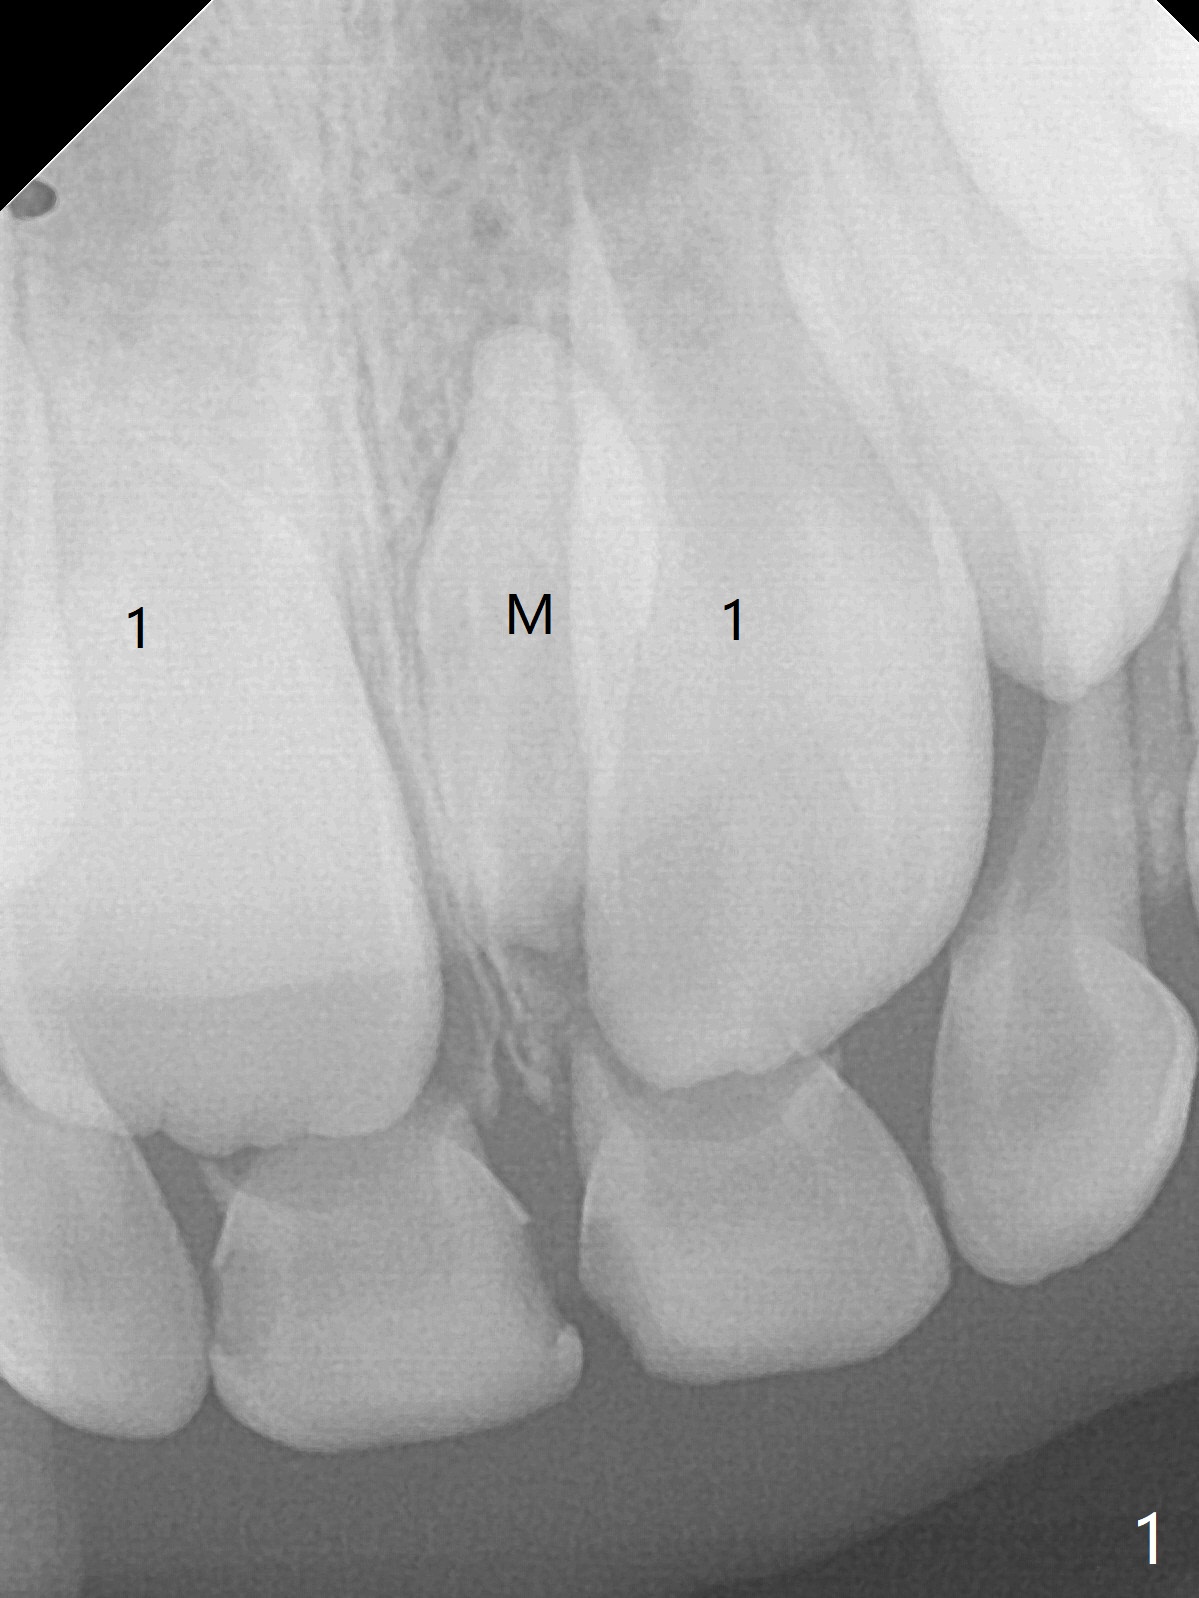

6岁11月女上乳中切牙松动许久,但不脱落,根尖片显示正中多生牙(图一:M),CT显示后者位于腭侧(图二:P)。Take preop photos to show whether the lower lateral incisors have erupted or not. If yes, remove the upperdeciduous central incisors. 一个月后病人回来时,右上乳中切牙已脱落,左上松动 ,术中后者好像影响视野而拔除,腭侧切口,暴露左上1后,拔除多生牙(图三)。 术后3个星期左上中切牙萌出,扭转,反合(图四,五)。术后六个月仍旧如此(图六,七),右上中切牙未萌出,小孩害怕促进萌出手术。准备制作活动矫正器。